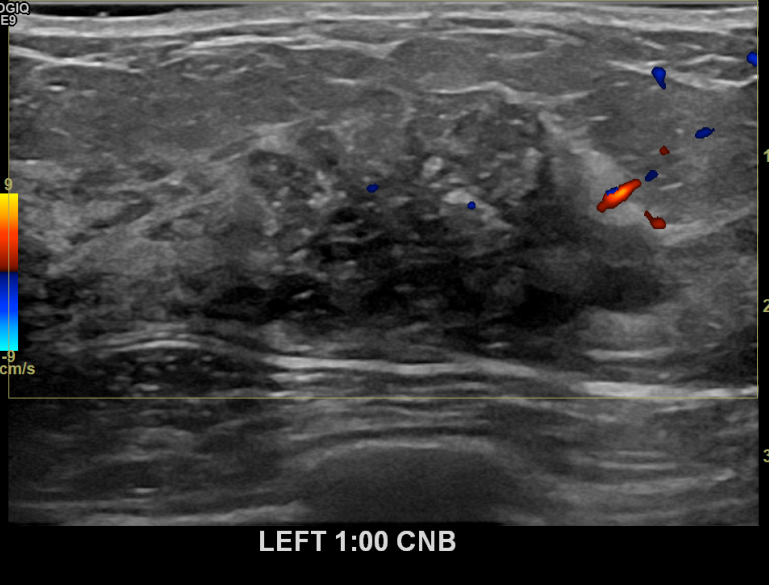

상기환자 외부검진상 이상소견으로 조직검사권유받고 내원하신 30대 여성분으로 좌측유방멍울 조직검사 시행 후 유방암 진단되었습니다.